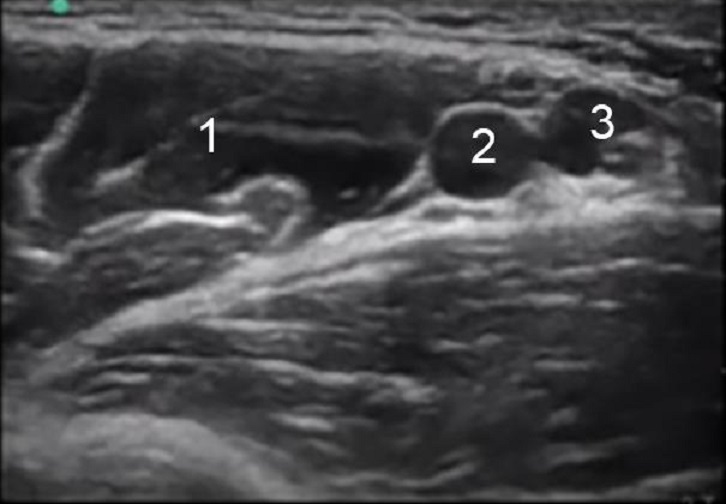

Axillary Bicep Muscle Image

Bicep Muscle

Axillary Artery

Axillary Vein